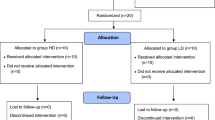

Twenty-six patients were included in this study with surgical correction by one surgeon between January 2014 and December 2017. Clinical data and radiographic images (preoperative, postoperative and one-year follow-up) were retrospectively analyzed and metal load, flexibility index, correction rate and correction index were consequently calculated. The Pearson correlation analysis was used for metal load—correction index and metal load—correction rate, correction of kyphosis—metal load and correction of lordosis—metal load. According to the mean metal load of 88%, patients were divided into two subgroups—a low-density group of 12 patients and a high-density group of 14 patients. Clinical and radiographic features were examined by an independent two-sided t-test.

A total of 62 surgical scoliosis treatments in one institution between January 2014 and December 2017 were retrospectively analyzed. Every operation was performed by the same senior surgeon. Each patient had to perform a preoperative magnetic resonance imaging of the whole spine to exclude malformations of the medulla, e.g., a tethered cord. Before the surgery, standardized posterior-anterior, lateral and left- and right-bending radiographs were carried out. Postoperative imaging control (posterior-anterior and lateral whole spine) was performed one week and one year after the surgery. The Cobb-angle measurement for each radiographic image was performed by two examiners in order to minimize the measurement error. After applying the exclusion criteria, which are listed below, a total of 26 patients could be included in this study.

All data are presented as mean ± standard deviation. Pearson correlation analysis (Lund, Sweden) was performed for the relationship between metal load and correction index, and metal load and correction rate. Correlation of the sagittal correction and implant density, flexibility index and curve correction directly after the surgery and at the follow-up was also depicted by Pearson coefficient. This calculation was also performed for the dependency of flexibility index and metal load. Sixteen patients had a double curve, 10 patients had only one structural curve. Double-curved scoliosis’ were divided into two curves and measured individually. The patients were divided into two groups according to the mean metal load. The features of these groups were investigated by an independent, two-sided t test. A p value < 0.05 was considered statistically significant.

The correlation between metal load and correction rate was 0.324 directly after the surgery (Fig. 3) and 0.285 at the follow-up (Fig. 4). The mean metal load was 88 ± 8%. Divided by the metal load, there was a low-density group (LD < 88%) and a high-density group (HD ≥ 88%).

Low-density group

High-density group

Comparison between low- and high-density group

The only statistically significant difference between the high- and the low-density group was found in the correction rate directly postoperative (p = 0.047). At the one-year follow-up, no significant variance could be detected (p = 0.21).

There was no statistical significance in age (p = 0.76), preoperative Cobb-angle (p = 0.54), convex bending (p = 0.63), Flexibility index (p = 0.13), operation time (p = 0.84), blood loss (p = 0.22), length of ICU stay (p = 0.63) or complication rate (p = 0.80).

The postoperative Cobb-angle and correction index showed no significant distinction directly after the surgery or at the follow-up (Cobb-angle directly postoperative p = 0.22, at the follow-up p = 0.55; correction index directly postoperative p = 0.22, at the follow-up p = 0.18).